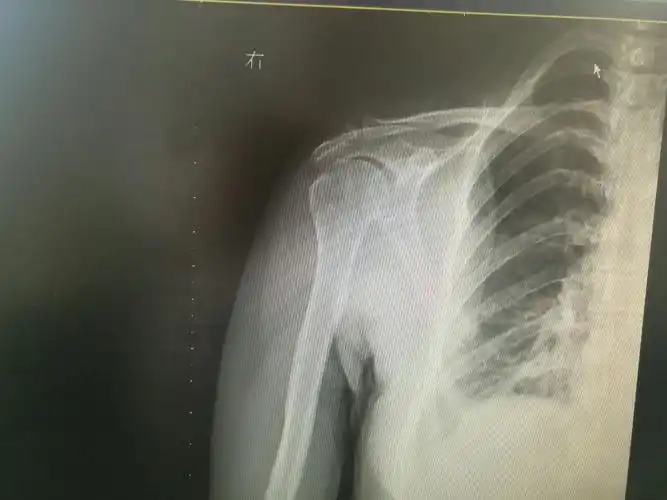

肩关节x线检查体位大全

重视肩关节疼痛,认识肩袖损伤. 沭阳县人民关节外科